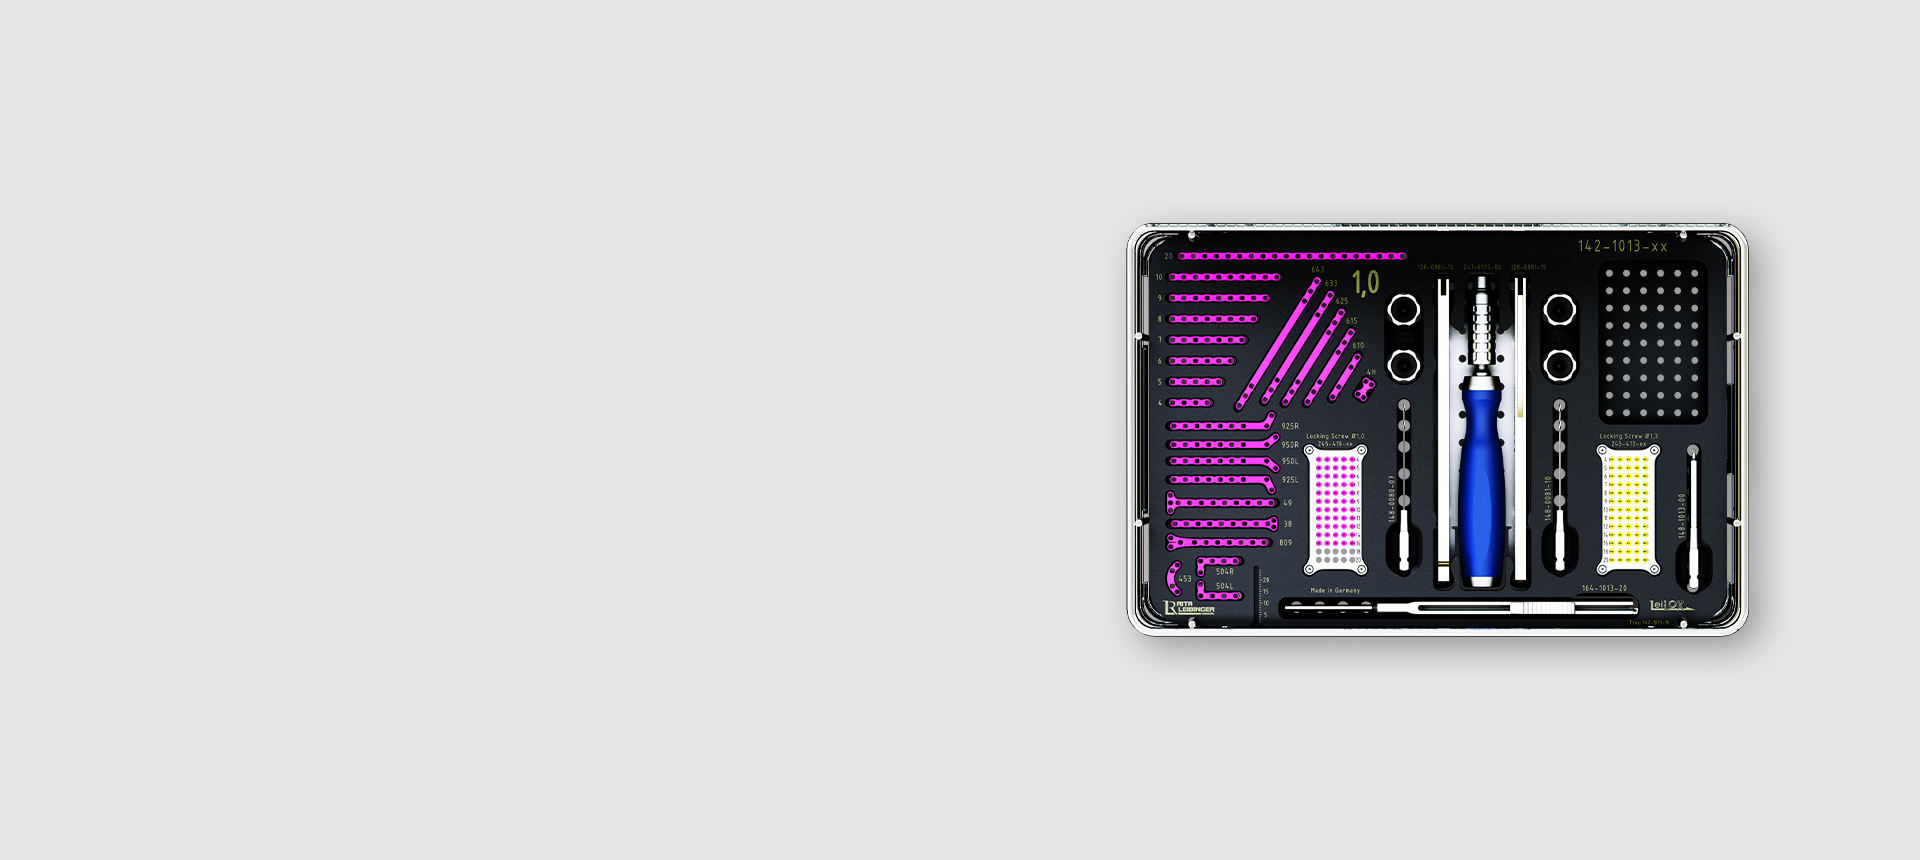

Products

Technology Leading Manufacturing

A Titanium LeiLOX CBLO Plate is born in one of our in-house machines: